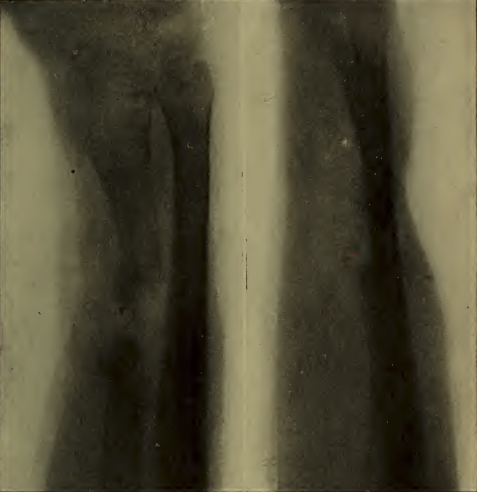

Radiographie d'une jambe dans du plâtre. Fracture des deux os avec déplacement. A gauche: vue de face. A droite: vue de profil. — PLANCHE VI.

Les planches VI et VII reproduisent des radiographies de fractures suivant des documents originaux. On peut s'y rendre compte de la différence d'aspect d'images obtenues de face et de profil. Les planches VIII et IX représentent des fractures en voie de guérison, avec formation de cal.